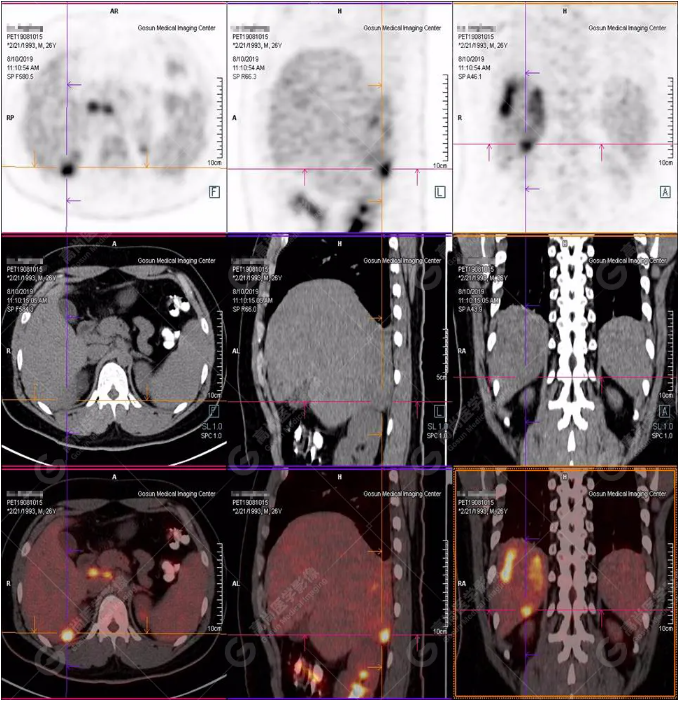

B超及CT檢查發(fā)現(xiàn):肝臟多發(fā)低密度占位。

PET/CT全身圖

PET/CT診斷

嗜酸性粒細(xì)胞增多癥肝浸潤(rùn)